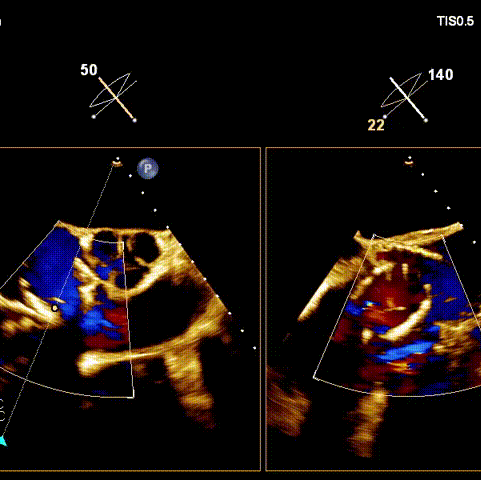

術(shù)后超聲

術(shù)前經(jīng)過全面系統(tǒng)的評估后,考慮患者存在高齡、心功能減低、三尖瓣瓣環(huán)重度擴張(三尖瓣極重度反流)等高危因素,因此廈心結(jié)構(gòu)心團隊聯(lián)合超聲心動、麻醉及護理團隊,制定了詳盡的圍術(shù)期治療方案及術(shù)中治療難點預(yù)案。術(shù)中,由王焱院長主刀,在蘇茂龍主任超聲心動團隊的輔助,上海市第一人民醫(yī)院陸方林主任的協(xié)助下,僅用時30分鐘,即順利完成了三尖瓣原位置換的手術(shù)。術(shù)中患者血流動力學(xué)穩(wěn)定,術(shù)后即刻顯示LuX-Valve Plus瓣膜位置良好,固定穩(wěn)定,瓣膜功能正常,無瓣周漏。

觀摩手術(shù)的臺灣專家對此次手術(shù)過程及LuX-Valve Plus器械展示出的優(yōu)異性能表示贊譽,表示與傳統(tǒng)外科三尖瓣治療方式相比,LuX-Valve Plus介入三尖瓣治療創(chuàng)傷小,安全性高,手術(shù)時間短,術(shù)中術(shù)后患者血流動力學(xué)可平穩(wěn)過渡;且與現(xiàn)有的三尖瓣緣對緣修復(fù)手術(shù)相比,LuX-Valve Plus原位三尖瓣置換對術(shù)中影像依賴度相對更低,操作更加便捷,并且憑借獨特的錨定及瓣葉固定方式可以最大程度的避免高度房室傳導(dǎo)阻滯的發(fā)生,同時也擁有較為豐富的產(chǎn)品規(guī)格,可以適應(yīng)不同三尖瓣瓣環(huán)擴張程度的患者,自適應(yīng)防漏環(huán)還可以有效預(yù)防瓣周漏的發(fā)生,產(chǎn)品的諸多特點讓與會專家再次對國產(chǎn)原創(chuàng)醫(yī)療器械刮目相看,并期望可以早日引入海峽對岸,讓臺灣地區(qū)的患者也可以使用到祖國的原創(chuàng)器械,救治更多的患者。